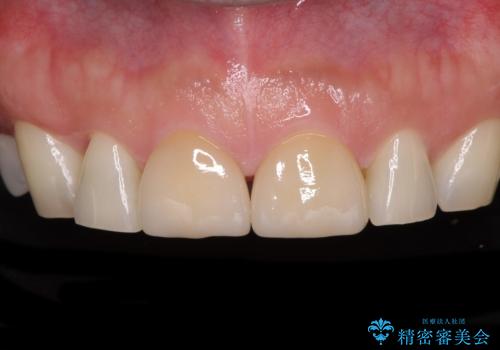

- 前歯の目立つ隙間を気にして来院された患者様です。

高校生の頃に矯正治療を行ったものの、強い咬合力により上顎が拡大され、正中に隙間ができてしまいました。

通常では歯の周囲全体を削った上でクラウンを装着することが多いのですが、咬合力が非常に強く、クラウンではセラミックが欠けてしまう可能性が考えられたため、咬合を変えることとのないラミネートベニアにて治療を行うこととしました。